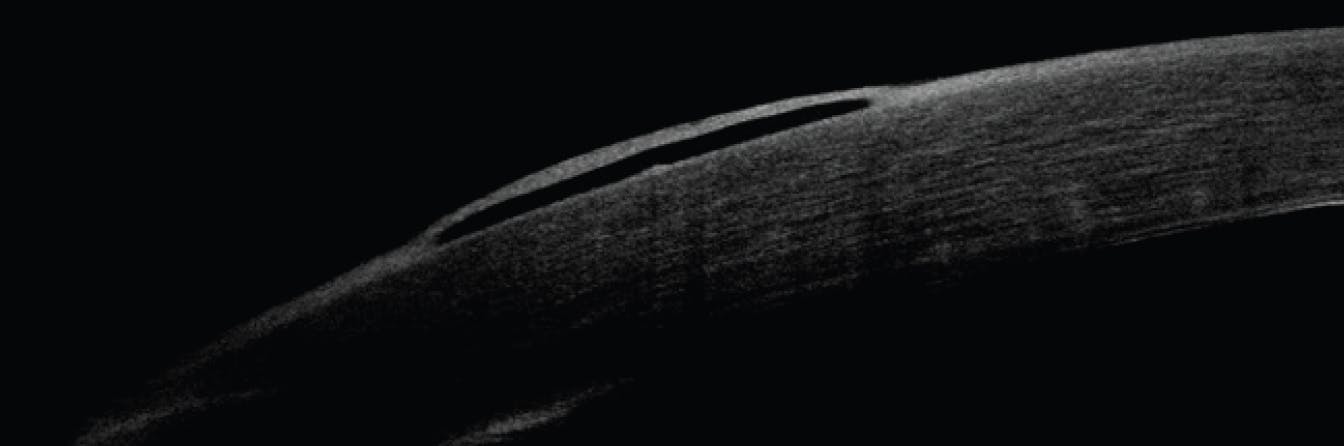

Serial pachymetry is also helpful in monitoring FECD progression into the later stages of the disease.5 As the cornea struggles to maintain deturgescence, more fluid accumulates, causing edema and higher pachymetry readings. Corneal thickness can be measured with several optical instruments: an ultrasound pachymeter, anterior segment OCT, tomographer, and specular microscope.6

If medical treatment is insufficient, a referral for an endothelial keratoplasty may be indicated. Surgical intervention should be considered in cases of poor vision affecting daily activities or eye pain due to microcystic edema or bullae (Figure 4). Most commonly, recommended treatment is a Descemet stripping endothelial keratoplasty (DSEK) or a Descemet membrane endothelial keratoplasty (DMEK). The visual outcome of a DMEK tends to be more optically clear than that of a DSEK due to the reduced thickness of DMEK tissue. Therefore, a DSEK is typically reserved for more complicated cases and those with lower acuity potential due to concurrent disease.11